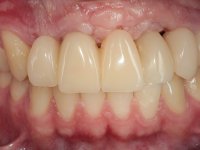

10 weeks after the surgery, a first impression was done to do a CAD-CAM provisional bridge (based on the diagnostic wax-up), that worked the soft tissue architecture during two months. This architecture was copied in a second impression by individualizing the impression copings in their emerging profile.

The working model was scanned and the dental technician developed a zirconia framework based on the diagnostic wax-up. This framework try-in was done, the perfect fit was assessed, and a final impression was done with a light silicone.

The bridge was finally placed with a progressive screwing to allow the tissue to accommodate the pressure of the pontics and the abutments emergency profiles.